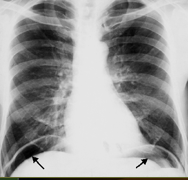

What does this show?

sickle-shaped free air on both sides under the diaphragm